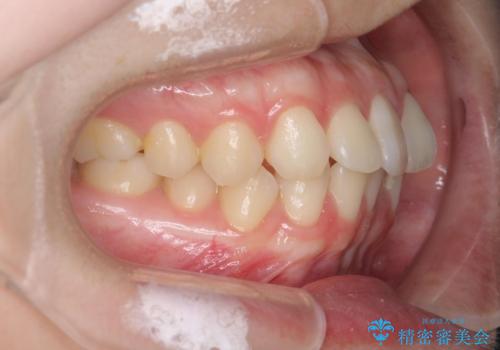

前歯のねじれをマウスピース矯正で治したい

- 前歯のねじれや がたつきを治したい、マウスピース矯正治療を希望され来院されました。

初診時程度のがたつきやねじれであれば、26枚以下のマウスピース矯正 モデレートプランで、比較的リーズナブルに矯正治療を受けていただくことができます。

実際の治療期間は約半年で仕上がりのような綺麗な歯並びを手に入れることができました。